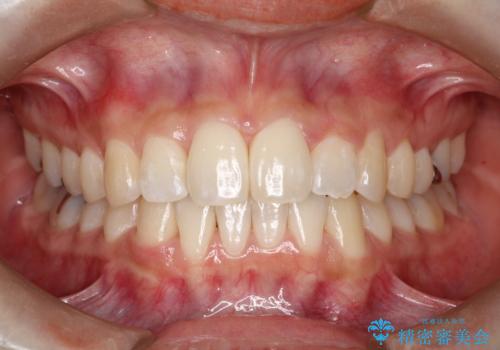

抜歯なし/インビザラインによるマウスピース矯正にて治療を行いました。

内側に入り込んでしまっている歯を出してくることに非常に時間がかかりましたが、一度歯を歯茎の方へ押し込みそして前へ出してくる2段階の治療を行いました。

見た目、噛み合わせ及び、治療期間や施術内容に大変ご満足いただきました。